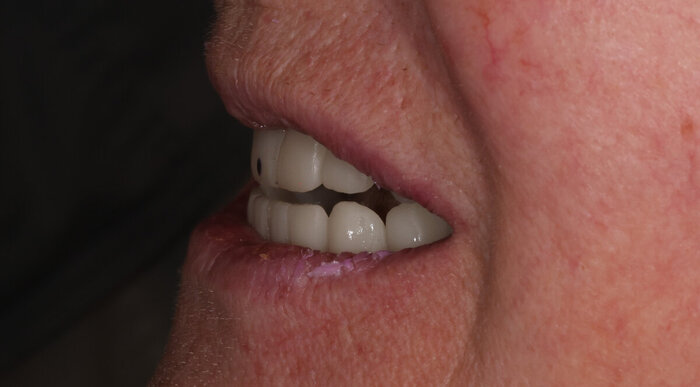

Теперь посмотрим, как это выглядит во рту:

2 недели после тотальной работы на имплантатах - 2 челюсти

Поднутрения, дефекты слизистой - на то протезы и временные адаптационные, что костная ткань должна перестроиться и прийти в себя перед постоянным протезированием.

Главное - всё комфортно. Этот вариант, действительно, отвечает физиологии мышц.